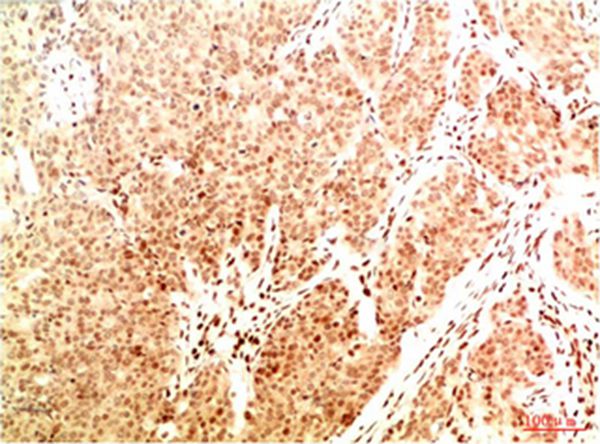

分类: 科研抗体货号: P43821别名:应用: WB,IHC反应种属: Human,Mouse,Rat